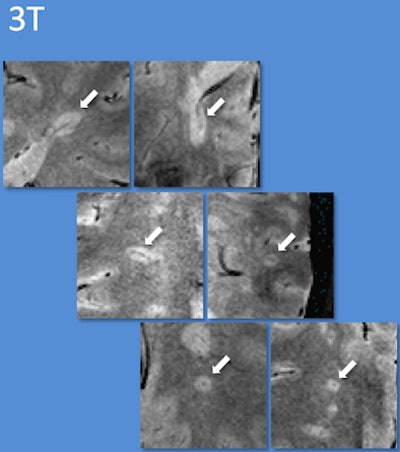

| Using 7-tesla and 3-tesla T2*-weighted MRI, multiple sclerosis lesions characteristically had appearances reminiscent of a donut or coffee bean. Using guidelines based on counting a few of these characteristic lesions, the diagnosis could be correctly identified. Images courtesy of Dr. Niraj Mistry. |

Using the 7-tesla MRI technique, 20 (80%) of the 25 patients could be diagnosed. Thirteen patients were diagnosed with MS; all of these patients had central veins visible in more than 40% of brain lesions. The seven patients with an eventual non-MS diagnosis had central veins visible in less than 40% of brain lesions.

Specifically, deoxygenated blood in veins has different magnetic properties than oxygenated blood in arteries. Using a 7-tesla MRI technique known as T2*-weighted imaging, researchers can make veins appear especially dark, while MS lesions look bright. "Previously, it has not been possible to see this in live patients using a single brain scan," Mistry added. "Now, with T2* MRI, we can."